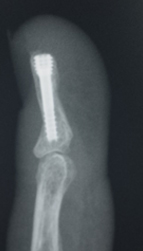

Distal falanks, parmak ucundaki kemiktir. Uygun parmak fonksiyonu ve tırnak büyümesi için sabit bir distal falanks gerekir. Çoğu distal falanks kırığının düzeltilmesi gerekmezken, bazılarının düzeltilmesi gerekir. Bunlar, düzgün bir şekilde birleştirilmesi gereken birçok parça ile oldukça karmaşık olabilir. Kötü bir şekilde düzeltilmiş kırıklar iyi iyileşmez, çok fazla ağrıya neden olur ve işe dönüşü geciktirir.

Eldeki kapalı kırıklar, yerinden oynamışsa veya deformiteye neden oluyorsa, uygun hizaya geri konulmalı ve ele iyi bir fonksiyon kazandırmak için metal teller, vidalar veya plakalarla sabitlenmelidir. Bu, el yaralanmasından birkaç gün sonra, mümkün olan en kısa sürede erken rehabilitasyona izin vermek için en iyi şekilde yapılır.

Uygun implantlarla sabitlenen kırıklar erken el tedavisine izin verecektir. Komplikasyonlar arasında hareketi engelleyen uzun vidalar veya teller, kırık parçalarının kötü hizalanması, tendonların sıkışmasına ve hareketi engellemesine neden olan çok büyük implantlar ve cilt ve dokuların uygunsuz yönetimi nedeniyle oluşan ciddi enfeksiyonlar yer alır. Bunlar potansiyel olarak iyileşmeyi ve işe veya spor aktivitelerine erken dönüşü yavaşlatabilir.